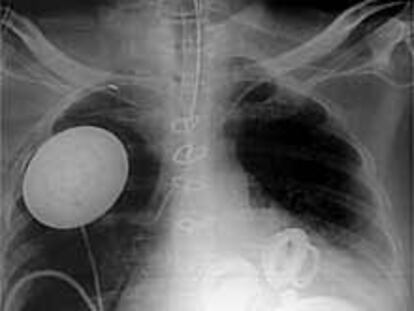

El corazón artificial, por rayos X.